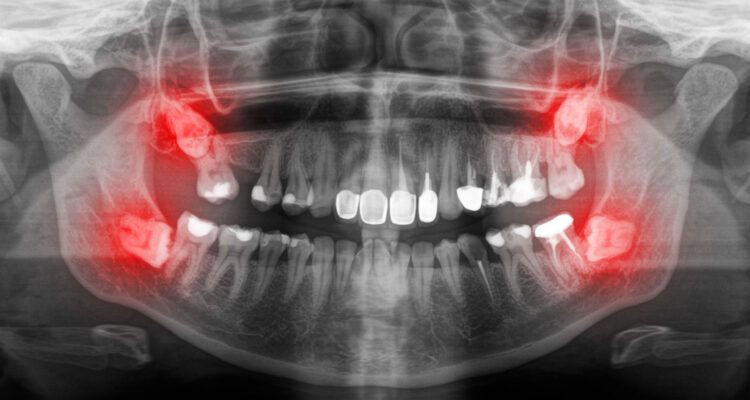

• атипичное расположение

• зуб растет горизонтально или под углом

Что такое дистопия?

Дистопия – это неправильное расположение одной или нескольких коронок. В таких случаях зуб выглядит выдвинутым вперед, наклоненным в ту или иную сторону или повернутым по оси.

Дистопия зубов мудрости может быть связана как с процессом прорезывания, так и с их локализацией. Дистопированный зуб в большей степени подвержен травмированию и повреждению слизистой оболочки, формированию налета и десневых карманов, развитию кариеса, пульпита и периодонтита, абсцессов и кист.